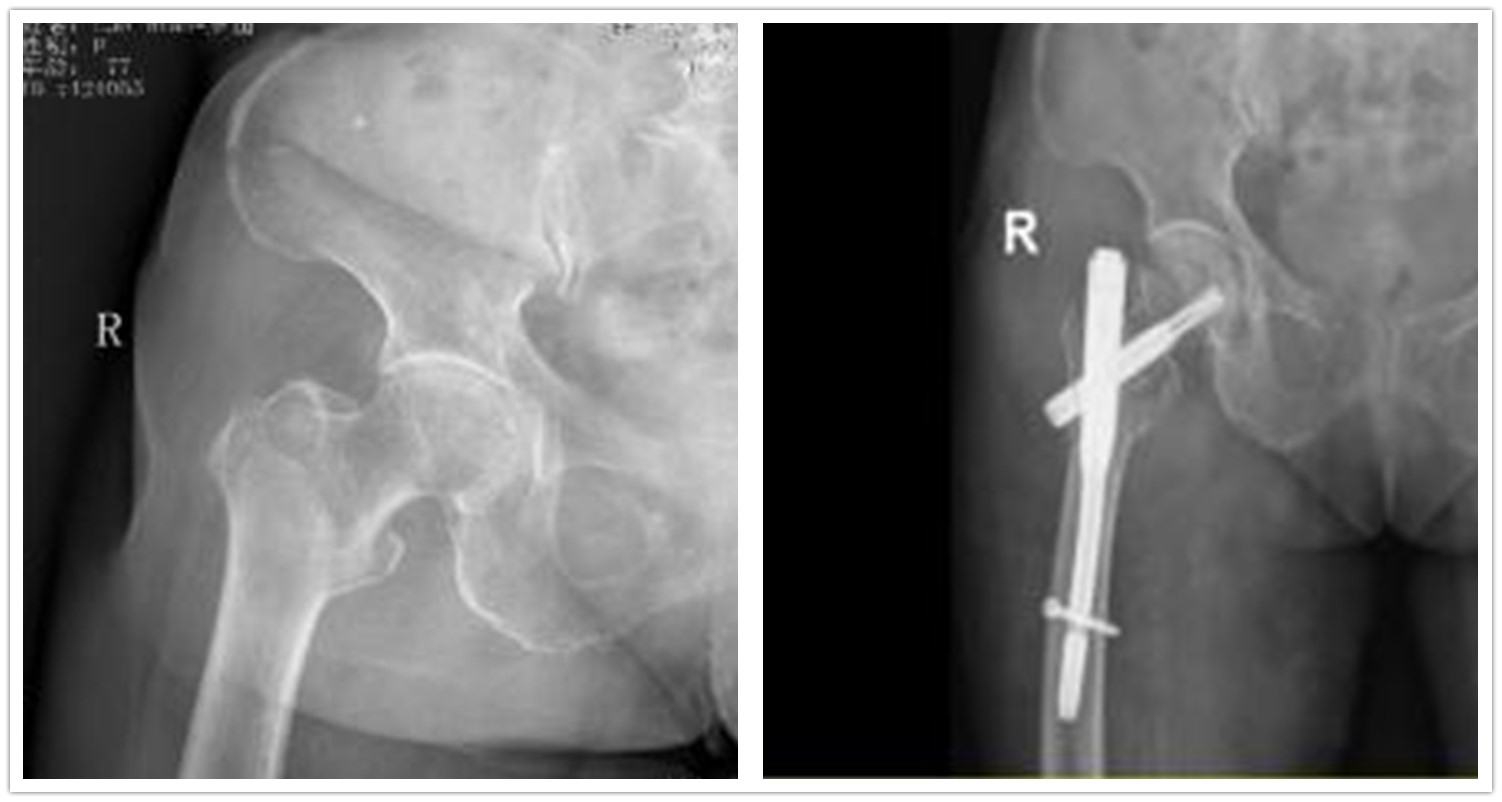

在医护人员严密监护下,罗婆婆的血压及血糖得到控制后,安排在2次透析间隙进行手术,采用微创下股骨近段髓内钉固定,手术过程顺利。术后医护人员予以对症支持治疗,规律透析,指导罗婆婆进行功能锻炼,最终其顺利康复出院。

术前(左图)术后(右图)对比图